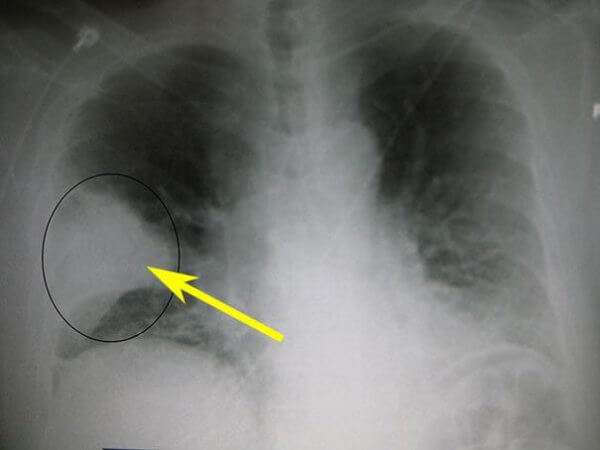

Первый признак пневмонии на рентгеновском снимке – появление очагов затемнения с неровными контурами в разных частях легкого, которые могут иметь разный размер, от 3-4-х до 12 мм.

Фото3

Тени различают по внешнему виду (круглые, овальные кольцевидные) и интенсивности окраски – чем темнее пятно, тем сильнее выражен патологический процесс.

Очаговая

Данному виду патологии свойственно поражение небольших участков легочной ткани. Изображение очаговой пневмонии прослеживается плохо, затемнения могут быть средней или вовсе слабой интенсивности. Размеры очагов поражения в среднем достигают полутора сантиметров, при отсутствии лечения их количество увеличивается. На фото ниже изображен пример правосторонней очаговой пневмонии.

Фото 3